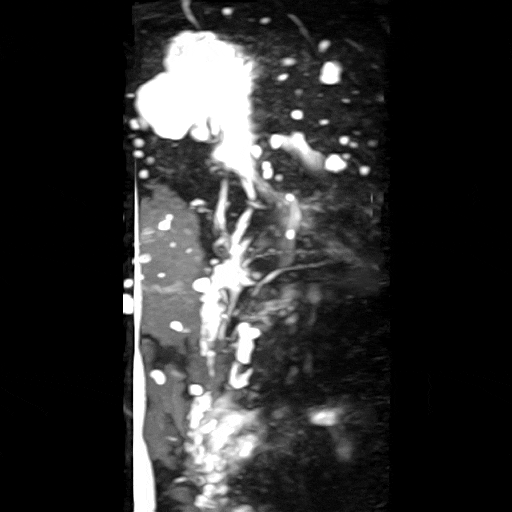

자기공명담췌관조영술상에서 췌장구상돌기 쪽으로 약 1.1cm 가량의 물혹이 보이고 있으며, 이는 췌장담도와 연결성이 보이고 있습니다. 이에 췌관내유두점액낭종으로 생각이 되며, 이에 대해서 추적 관찰을 하기로 하였습니다.

• MRI MRCP 3D: 췌장담도와 연결성 확인(빨간 동그라미) MRI MRCP 3D: 췌장담도와 연결성 확인(빨간 동그라미)